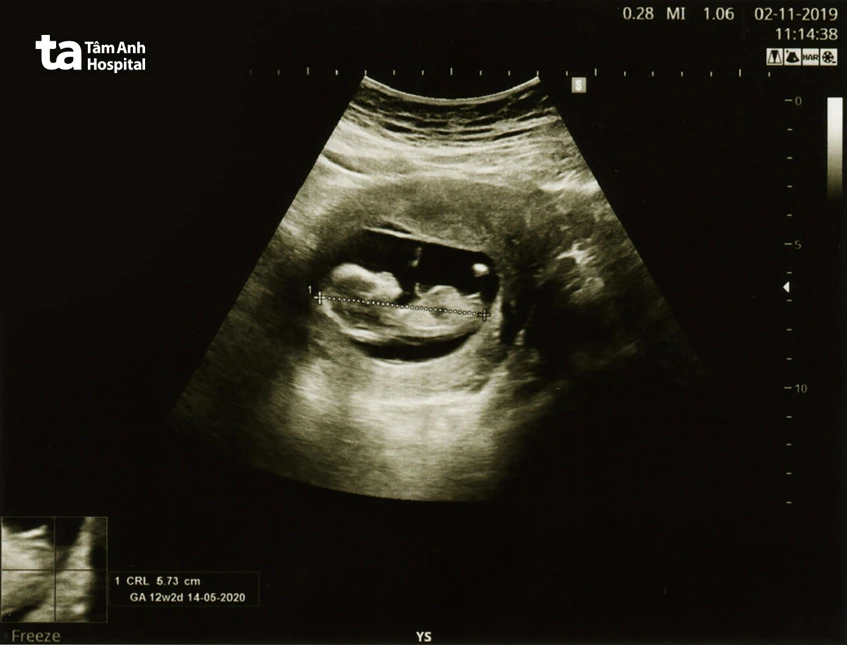

Tiếp đến, bước vào tuần 11-13 là một mốc khám quan trọng với mục đích siêu âm độ mờ da gáy. Đây là công việc không thể thiếu để sàng lọc cho các bệnh lý bẩm sinh từ sớm. Như việc thắp ngọn đèn trong trường tranh tối tranh sáng, nó giúp chúng ta thấy rõ hơn con đường phía trước của mẹ lẫn bé.

Lần khám thai đầu tiên có thể được gọi là khởi đầu của một hành trình mà người mẹ có cơ hội quen biết với vị bác sĩ sẽ cùng mình đi đến cuối hành trình sinh nở. Trong buổi khám này, bạn sẽ trải qua một loạt các xét nghiệm nhằm đánh giá tổng quát sức khỏe của mẹ và thai nhi. Siêu âm là bước đầu tiên, qua đó bác sĩ có thể đưa ra khẳng định nghiêm túc rằng có một sinh linh nhỏ bé đã xuất hiện, đồng thời kiểm tra vị trí của thai nhi trong tử cung.

Hiện nay, khám thai không còn là một bài toán khó với những bài giảng khô khan, mà đã trở thành một hành trình trải nghiệm với nhiều hình thức đa dạng. Khám thai định kỳ bao gồm một loạt các biện pháp từ siêu âm, xét nghiệm máu, các xét nghiệm sàng lọc đặc biệt. Siêu âm là một trong những công cụ chủ yếu, giúp bác sĩ và cả bố mẹ có dịp thấy rõ hơn hình hài của em bé, giống như việc đi qua từng tầng cửa của một giải pháp trải nghiệm thực tế ảo mở ra từng khoảnh khắc kỳ diệu.